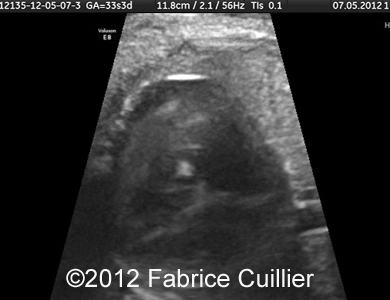

At 30 weeks, the kidneys were hyperechoic, but we could observe normal cortico-medullar differentiation (Figure 2, 3). At 31 weeks, the same anomalies were confirmed. Futhermore, we observed physiological scrotal hydrocele (Figure 4) and a echogenic foci on mitral valve without cardiac dysmorphology (Figure 5-10).

Figure 5-10: Cardiac echogenic foci